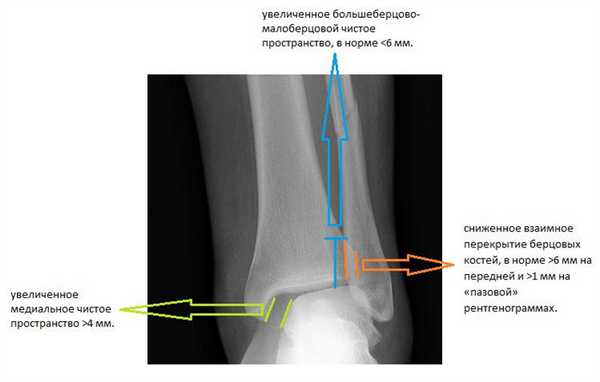

Признаками, указывающими на разрыв межберцового синдесмоза служат:

-сниженное взаимное перекрытие берцовых костей, в норме >6 мм на передней и >1 мм на «пазовой» рентгенограммах.

-увеличенное медиальное чистое пространство >4 мм.

-увеличенное большеберцово-малоберцовой чистое пространство, в норме